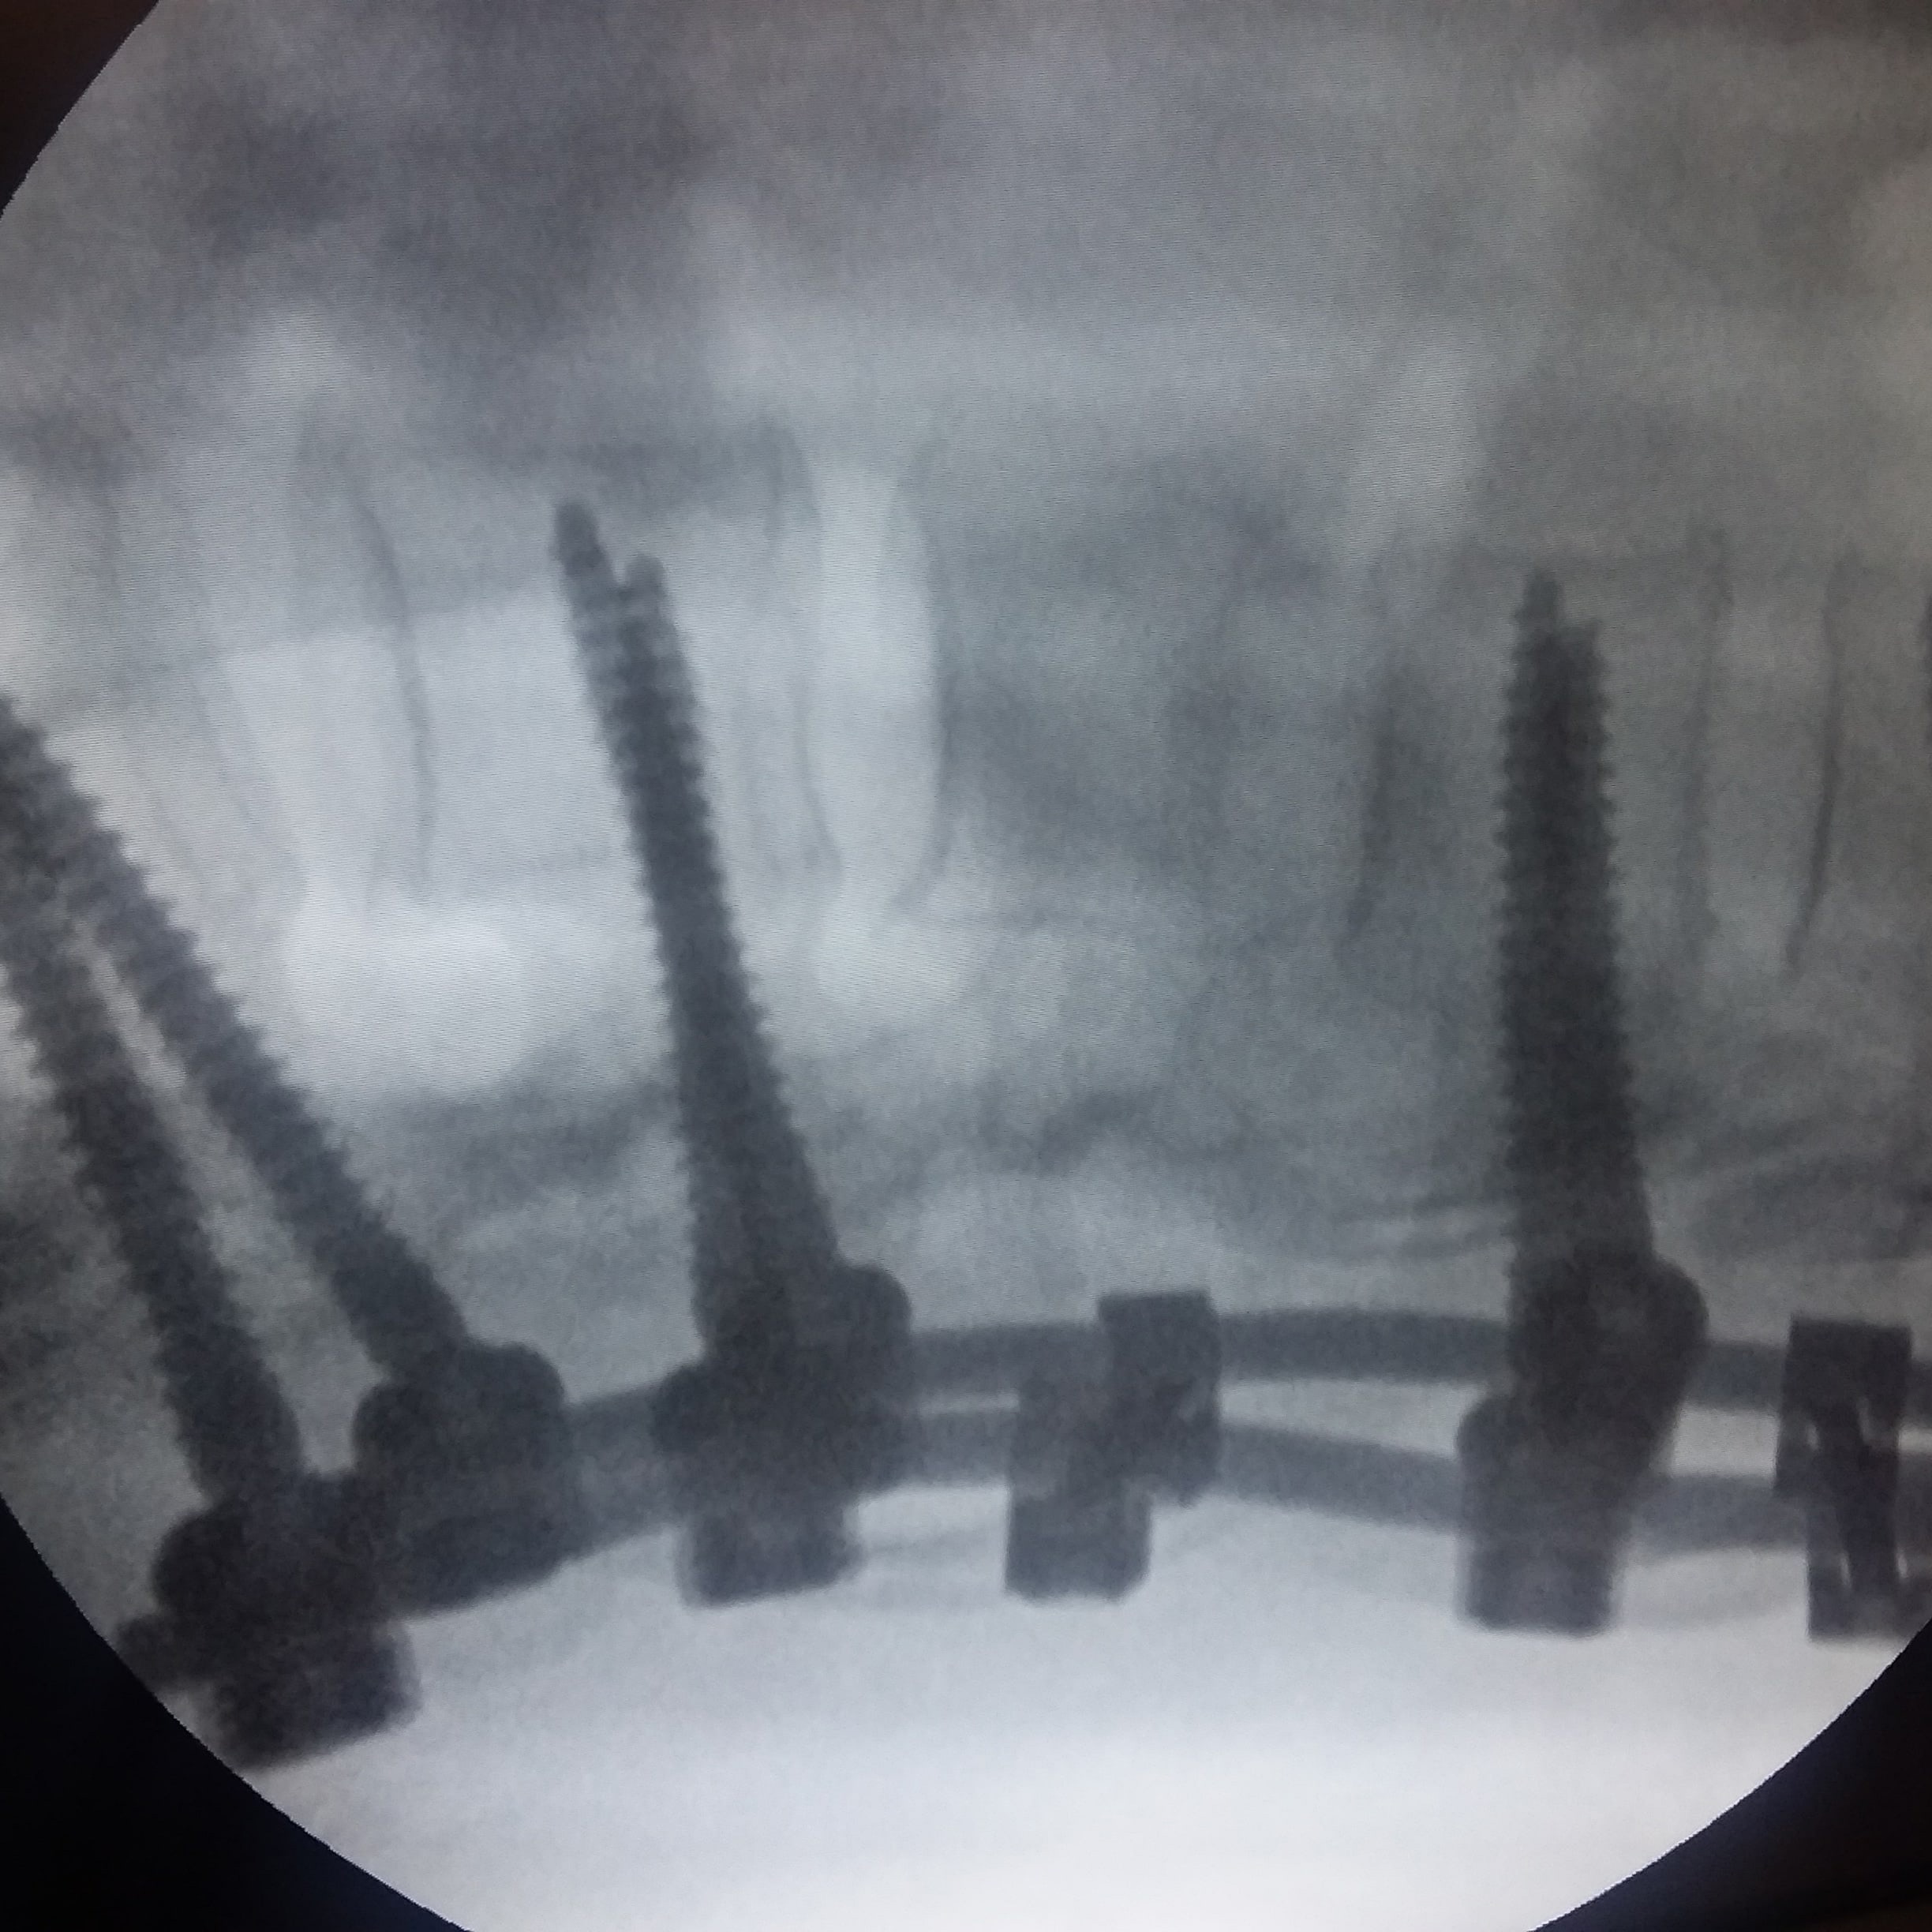

Красноярке после катания на «плюшке» пришлось винтами закреплять позвоночник

Лечение проходило в несколько этапов. Чтобы помочь пострадавшей, травматологи зафиксировали позвоночник системой позвоночных винтов.